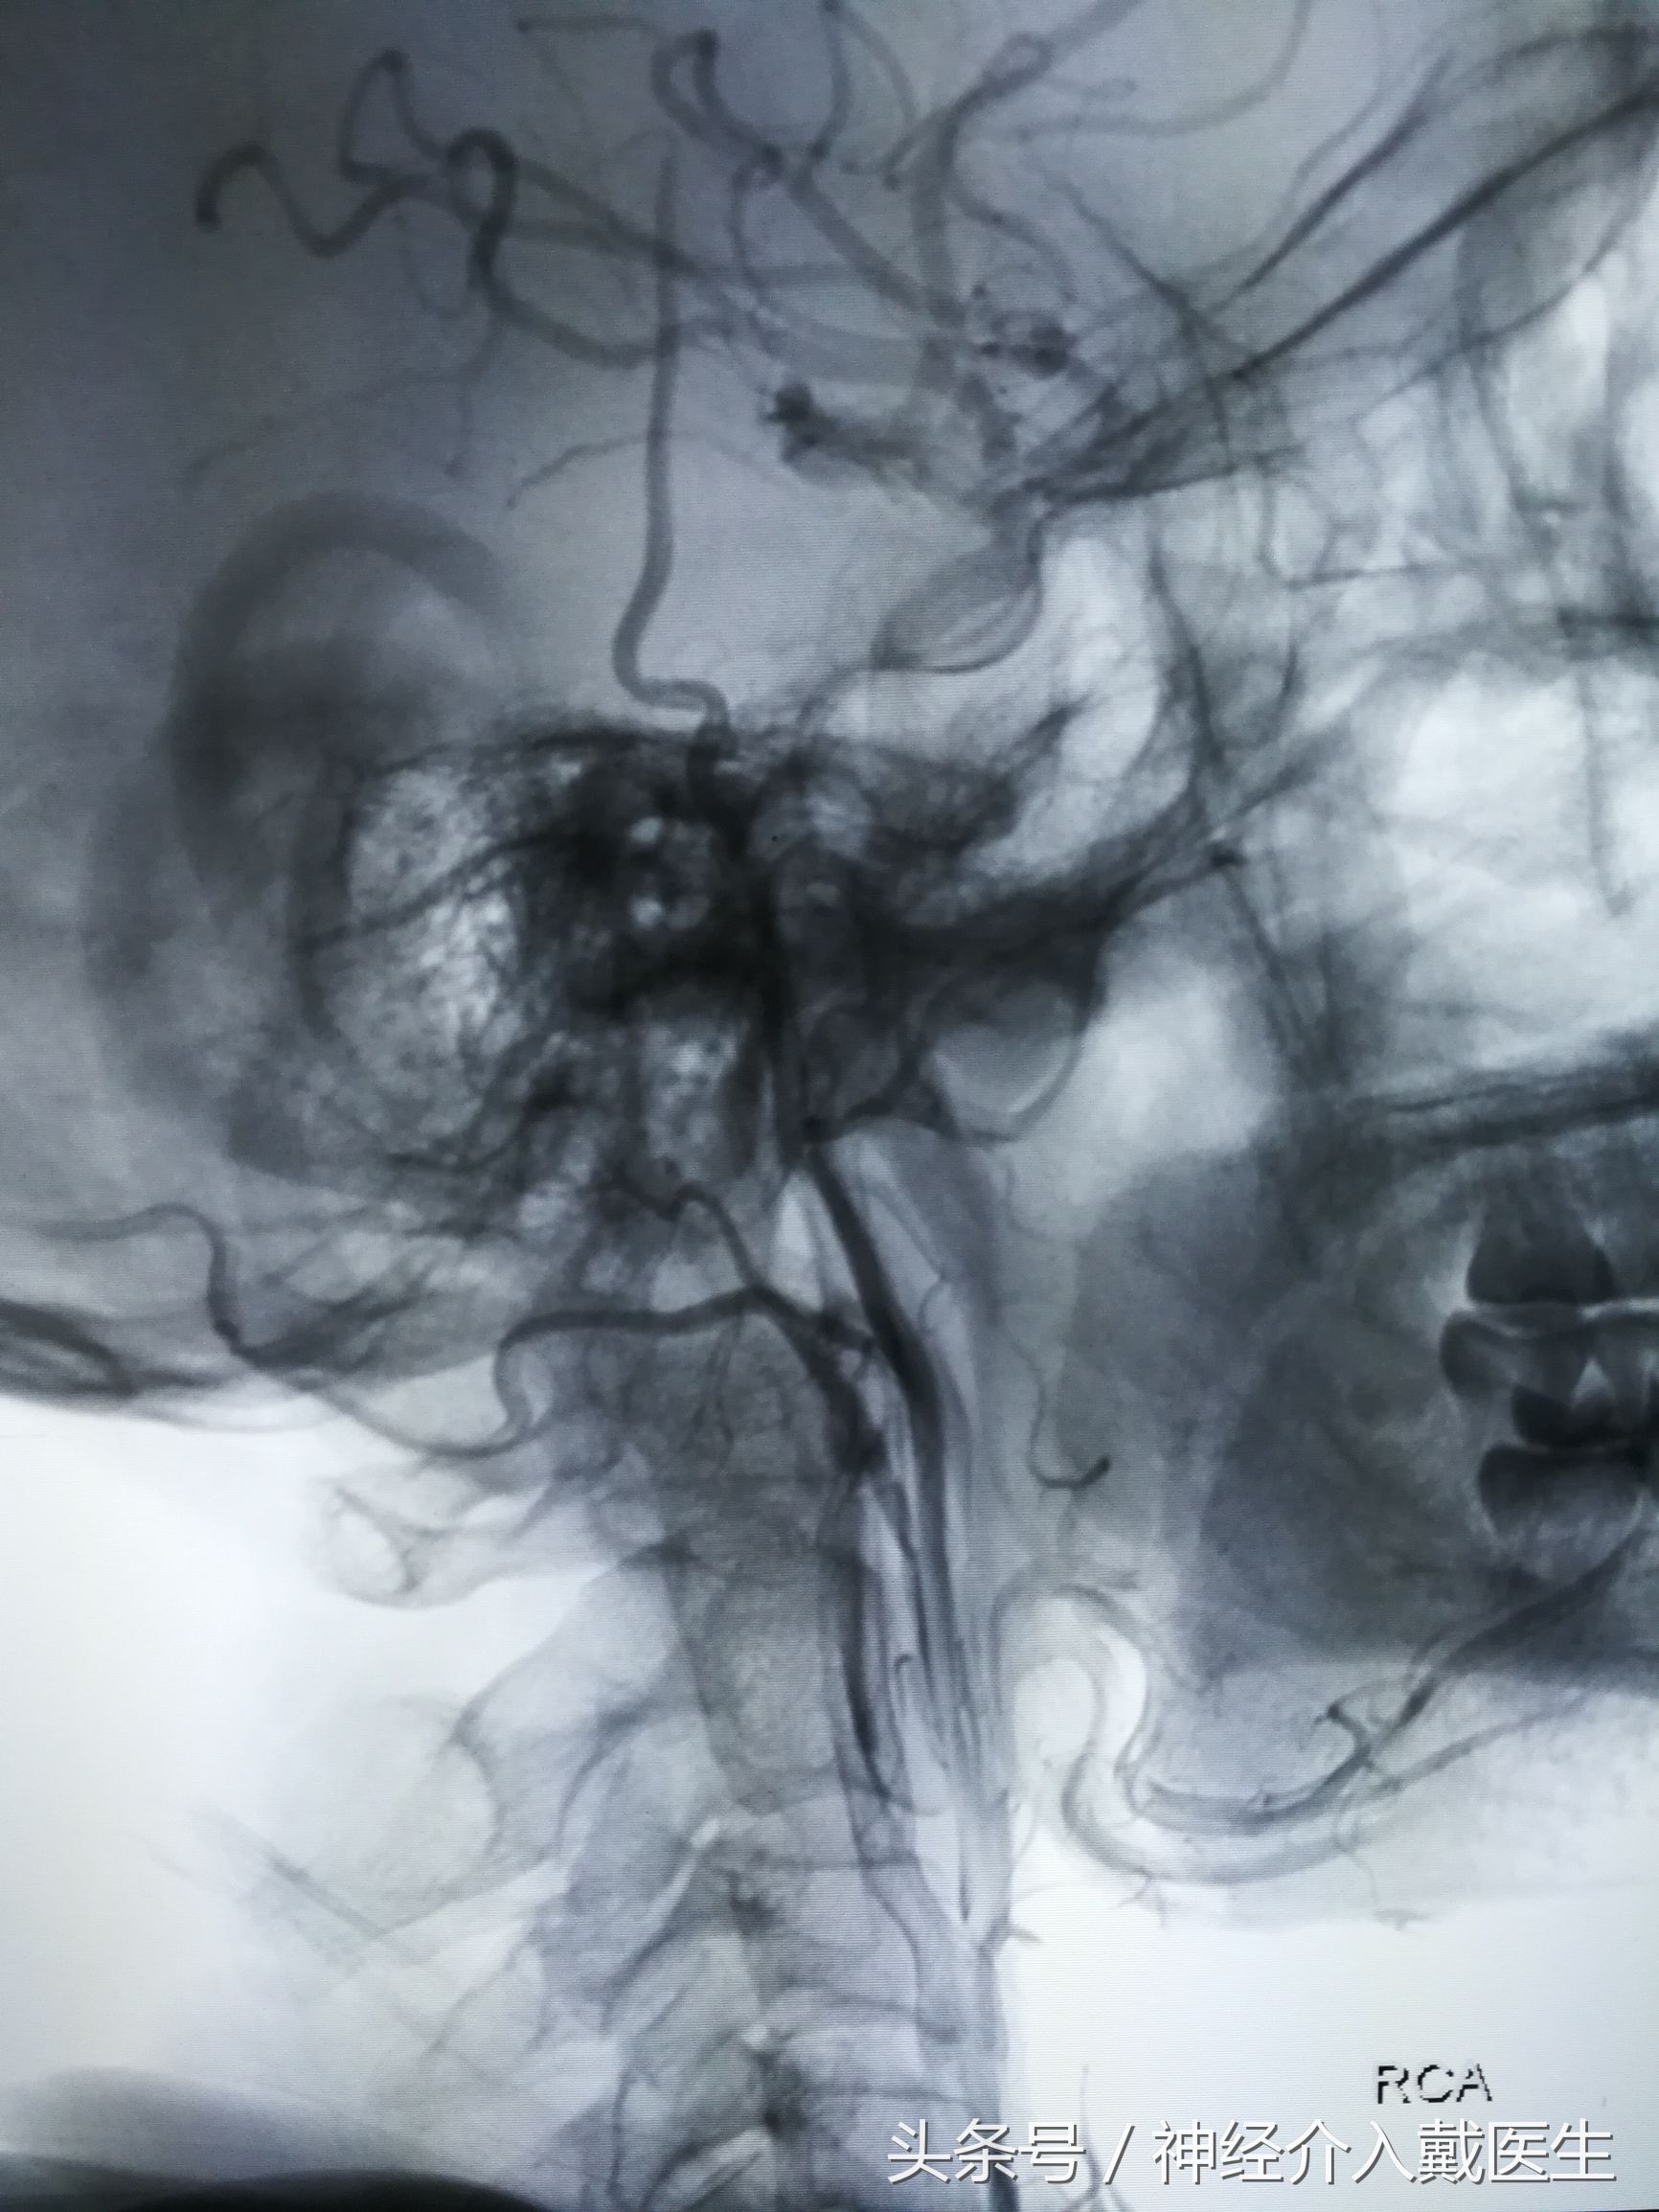

经过仔细分析,权衡利弊,最后选择颈动脉支架成形术。

这是颈动脉狭窄经球囊扩张后植入颈动脉支架

手术是在局麻下进行的,术中人神志是完全清醒的,因为手术扩张了颈内动脉,立即改善了脑部血流,术后头晕症状基本消失,没有再晕倒了,只要术后维持吃药,定期复查就可以了。